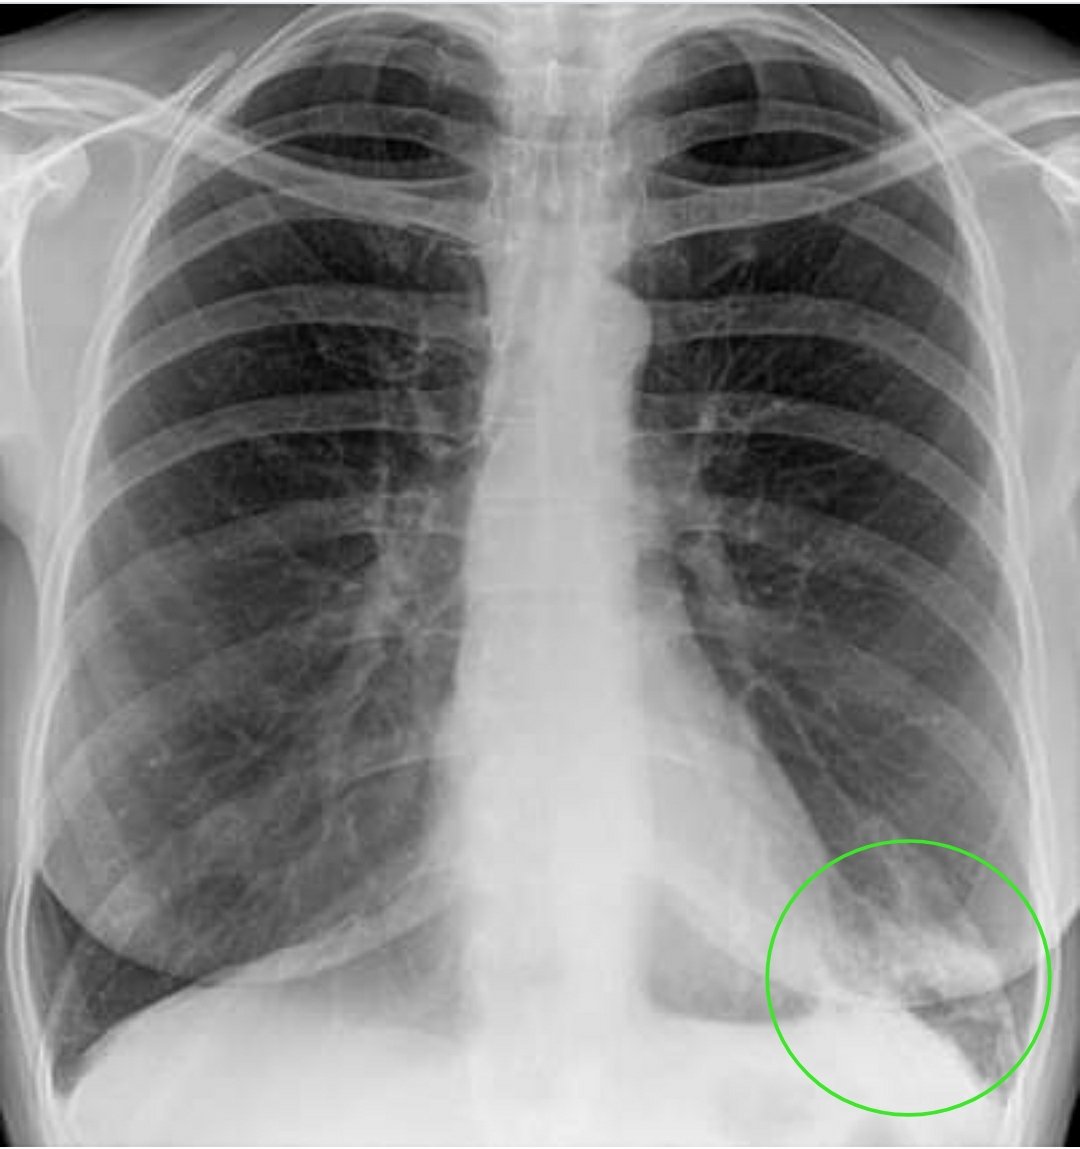

Фотографии бактерий, вызывающих бактериальные пневмонии у животных